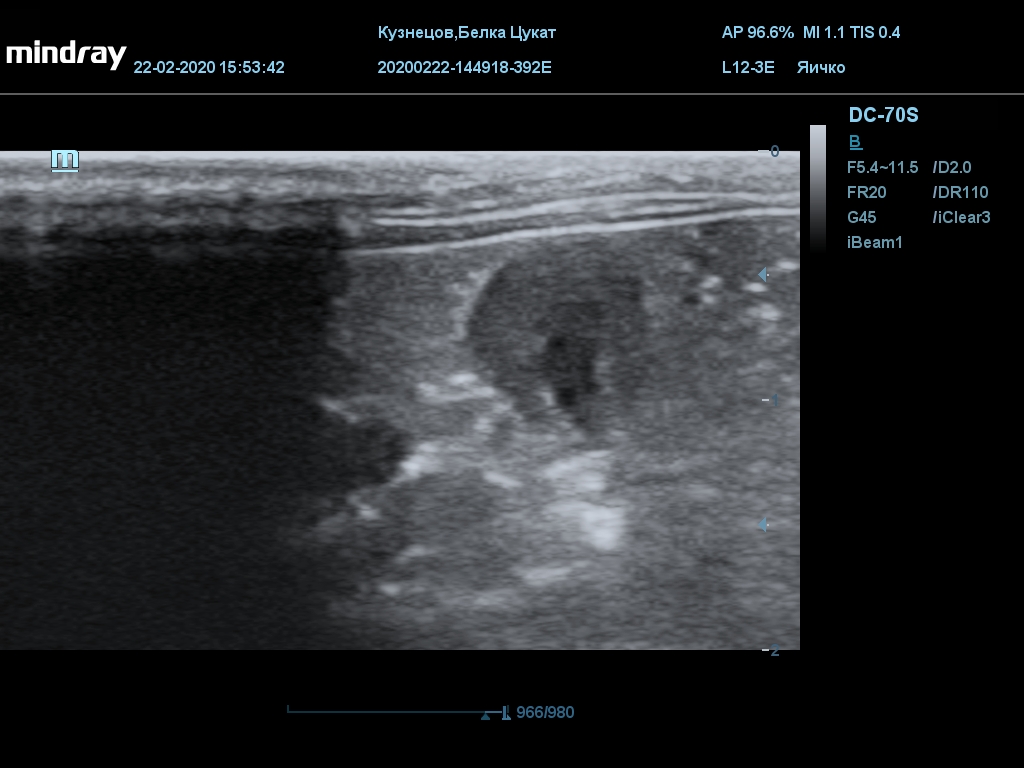

УЗИ

(почки, мочевой пузырь и, предположительно, простата)

Обращаю внимание, что делала УЗИ и писала заключение узист, которая специализируется на кошках и собаках, поэтому она сделала узи и описала, как смогла, но тонкостей грызунячьей анатомии она не знает.

Приложил только фото, есть ещё пара видео, но не знаю, как тут выложить, и надо ли.

Мочевой пузырь объём 12,1 х 7,6 х 11 мм. Стенка не утолщена, 0,5 мм, содержимое не однородное, до половины объёма гипоэхогенная мелкодисперсная взвесь. Макс. размер включений 0,8 мм. Теней нет.

Каудальнее мочевого пузыря визуализируется округлая структура размером 11,1 х 8,3 мм с ровными контурами гипоэхогенная однородная, с признаками васкуляризации.

Почка левая ровная, размер 12 х 7,6 х 8,2 мм. Контур ровный чёткий. КМД отсутствует, лоханка расширена незначительно, объёмных включений не выявлено.

Почка правая ровная, контур чёткий, размер 13,5 х 8,7 х 9,3 мм. Капсула визуализируется. КМД отсутствует, лоханка не расширена. Объёмные образования не выявлены.

Заключение: УЗпризнаки уролитиаза, объёмная структура каудальнее мочевого пузыря. Признаки расширения левой лоханки.

УЗИ

(почки, мочевой пузырь и, предположительно, простата)

Обращаю внимание, что делала УЗИ и писала заключение узист, которая специализируется на кошках и собаках, поэтому она сделала узи и описала, как смогла, но тонкостей грызунячьей анатомии она не знает.

Приложил только фото, есть ещё пара видео, но не знаю, как тут выложить, и надо ли.

Мочевой пузырь объём 12,1 х 7,6 х 11 мм. Стенка не утолщена, 0,5 мм, содержимое не однородное, до половины объёма гипоэхогенная мелкодисперсная взвесь. Макс. размер включений 0,8 мм. Теней нет.

Каудальнее мочевого пузыря визуализируется округлая структура размером 11,1 х 8,3 мм с ровными контурами гипоэхогенная однородная, с признаками васкуляризации.

Почка левая ровная, размер 12 х 7,6 х 8,2 мм. Контур ровный чёткий. КМД отсутствует, лоханка расширена незначительно, объёмных включений не выявлено.

Почка правая ровная, контур чёткий, размер 13,5 х 8,7 х 9,3 мм. Капсула визуализируется. КМД отсутствует, лоханка не расширена. Объёмные образования не выявлены.

Заключение: УЗпризнаки уролитиаза, объёмная структура каудальнее мочевого пузыря. Признаки расширения левой лоханки.